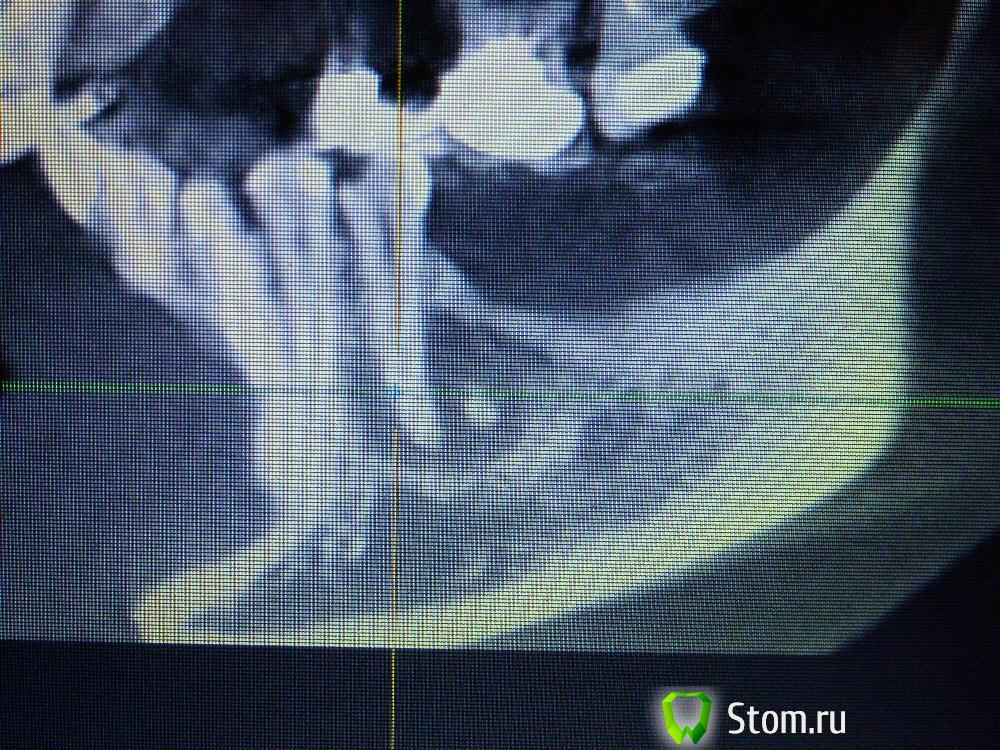

IvanK Опубликовано 25 ноября, 2011 Поделиться Опубликовано 25 ноября, 2011 Коллеги , посоветуйте Ваш план лечения.Пациентка обратилась с целью протезирования. Была направлена на ОПТГ. Обнаружены "кисты".Предположены амелобластома или первичная киста. Направлена на кафедру в 1 мед. Сказали, что "обычные кисты".Вижу 2 варианта:1). эндодонтическое лечение, цистэктомия, гистология, резекция верхушек корней, наблюдение, далее костная пластика?, имплантация. 2) Удаление зубов с периапикальными изменениями + 8-ка, гистология, пластика, имплантация боковых отделов. Ссылка на комментарий

Corvalus Опубликовано 26 ноября, 2011 Поделиться Опубликовано 26 ноября, 2011 Эндодонтическое лечение: 45,44,33-го тоже он в зоне кисты,34,36. Хуже дела обстоят с 35-м, глянуть бы прицельный снимок, если периапикальные изменения есть, то шуруп трудно достать будет. Обязательно реэндодонтия 43. Далее цистэктомия без всяких резекций с обязательной гистологией. Заполнять кисты не стал бы, достаточно крови, очаг гнойный. Через несколько недель парадонтологическое лечение, после костная пластика с отсроченной имплантацией. И в конце рациональное протезирование одиночными коронками. При нормальном эндодонтическом лечении рецедива кист не должно быть, а если и будет, то не на всех зубах сразу. Себе зубы удалять не стал бы, опыт лечения таких зубов есть, с имплантацией всегда решить можно по ходу поступления проблем. Второй вариант имеет место быть. Объяснить пациентке все за и против, пусть сама выбирает. Ссылка на комментарий